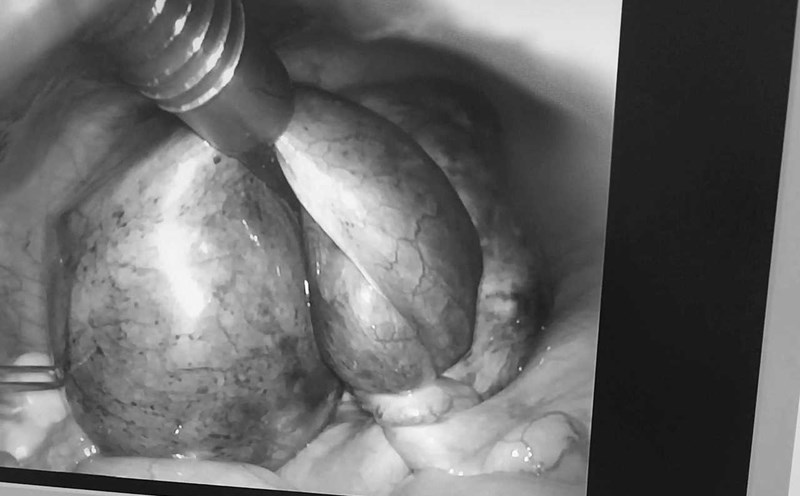

Timely rescue of two cases of genital torsion

|

On May 27, Le Van Viet Hospital in Ho Chi Minh City announced that it had just successfully performed emergency surgery on two rare cases of genital torsion.